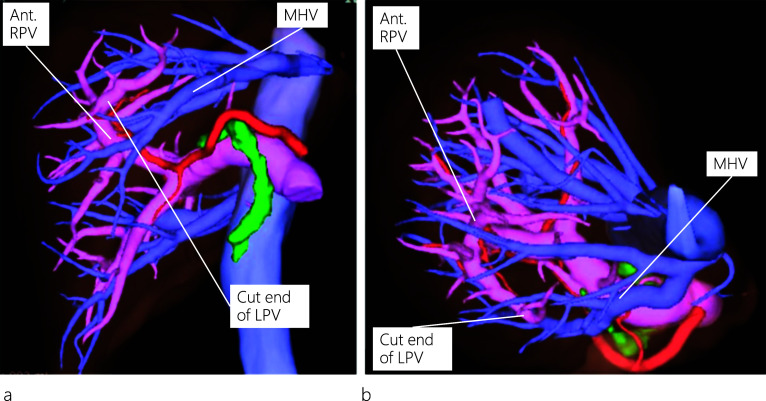

A 45-year-old female patient visited a local hospital with abdominal pain. Blood tests revealed elevated liver enzyme levels, and abdominal computed tomography (CT) revealed dilatation of both the common bile duct (CBD) and intrahepatic bile duct (IHBD). The patient underwent magnetic resonance cholangiopancreatography (MRCP) and endoscopic retrograde cholangiopancreatography (ERCP). MRCP showed CBD stones and stenosis at the confluence of B2 and B3 (Fig. 1a), while ERCP revealed IHBD stones in B2 and B4 (Fig. 1b), which were also observed on abdominal ultrasound (US) (Fig. 1c). Brushing cytology and biopsy at the site of the IHBD stenosis were negative for malignancy. Although the CBD stones were removed, the IHBD stones could not be; therefore, she was referred to our hospital for surgical treatment. Further examination could not be performed around the site of the IHBD stenosis because of impacted stones. Therefore, laparoscopic left hepatectomy was scheduled for suspected intrahepatic cholangiocarcinoma resulting from the impacted stones. However, to properly delineate the anatomy of the liver, enhanced CT was performed, which revealed a dilated IHBD in the left lobe and communication between the right PV and the umbilical portion (Fig. 2a, b). Based on the enhanced CT data, three-dimensional (3D) CT images were reconstructed, which revealed that instead of being located in the left Glisson’s sheath, both the left hepatic artery and bile duct were separated from the left PV (LPV) (Fig. 3a). They also revealed an LPV running through the ventral side of the middle hepatic vein (MHV) (Fig. 3b). Based on these findings, the patient was diagnosed with APB and scheduled to undergo laparoscopic left hepatectomy.

Regarding the anatomy of the bile ducts in patients with APB, Terasaki et al. [ref. 12] reported two patients with different bile duct characteristics, in whom the left hepatic duct ran either inside the liver along the PV or separately down into the common hepatic duct. The differences in running patterns between the PV and the bile duct can be explained from an embryological perspective. In our patient, an ordinary left bile duct was present, and IHBD stones were identified in the dilated B2 and B4. It is noteworthy that on routine preoperative plain CT images, the APB anomaly was not detected owing to the limitation of the images in outlining the detailed anatomy of the liver vasculature. However, the anomaly was detected on the preoperative enhanced CT images, which allowed us to reconstruct 3D images and view the detailed anatomy of the liver vasculature from different positions (neutral and left anterior oblique positions), as shown in Fig. 3.